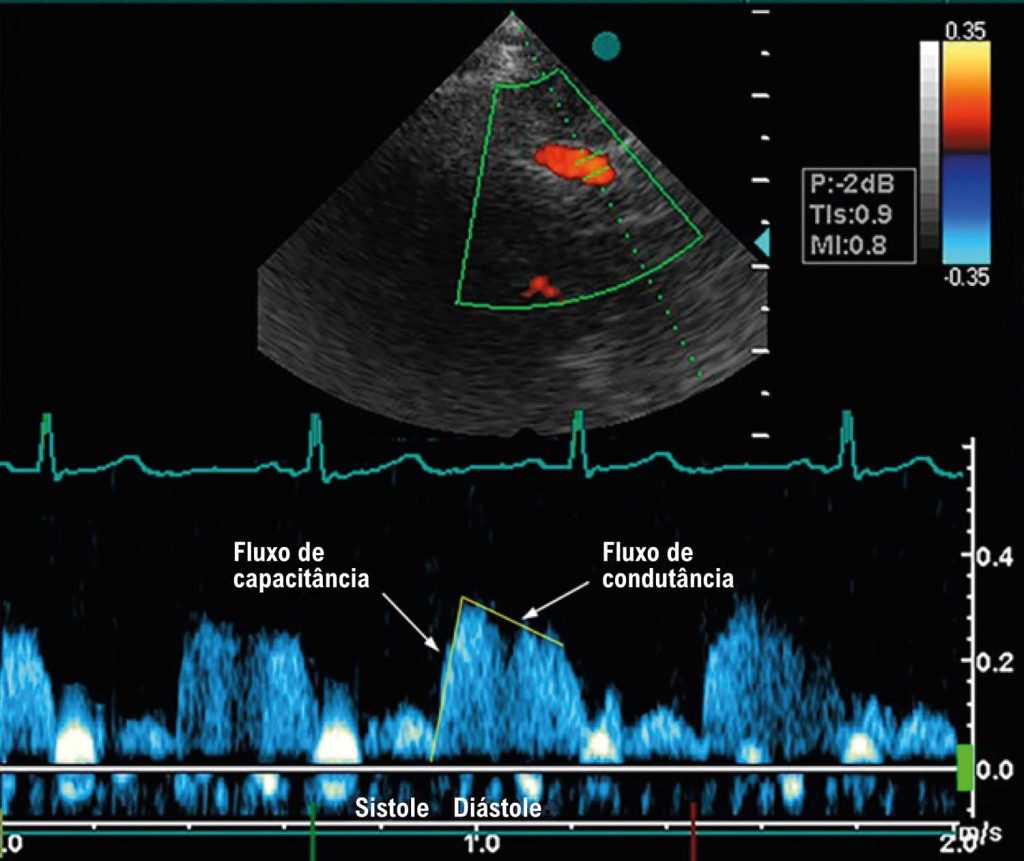

Como Eu Faço a Avaliação do Fluxo Coronariano ao Ecocardiograma Transtorácico

A avaliação da reserva de fluxo coronariano constitui uma etapa extremamente importante da ecocardiografia de estresse, dentro e fora do contexto da doença arterial coronariana. Para alguns, é vista como um parâmetro impossível; para outros, é essencial. De todo modo, tudo começa com a adequada visualização das artérias coronárias em repouso. Neste artigo, abordaremos conceitos teórico-práticos para a incorporação do estudo do fluxo coronariano à rotina do ecocardiografista.